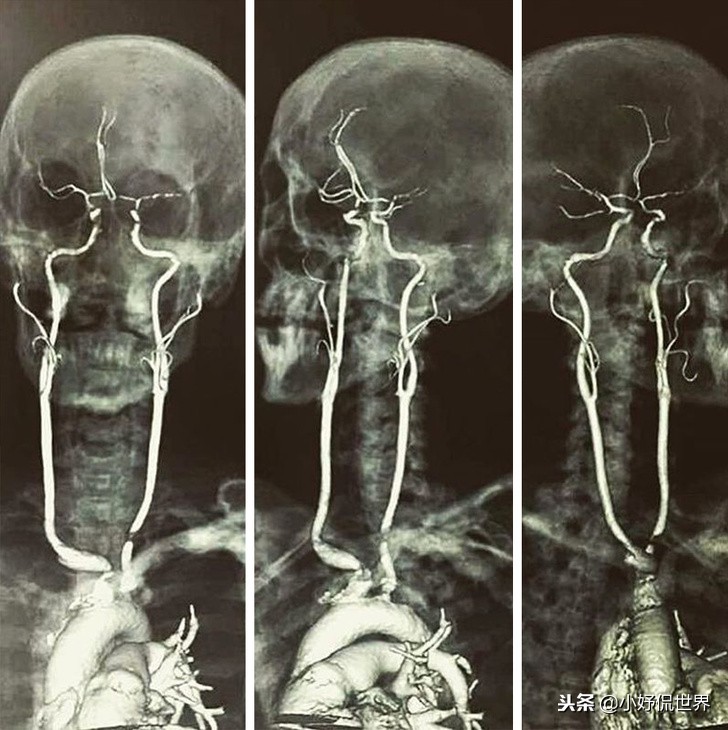

10、颈动脉

你有没有想过颈动脉是什么样的?通过磁共振成像展现的颈动脉可能和很多人想象的不同,但这更让人感受到了它的重要性。